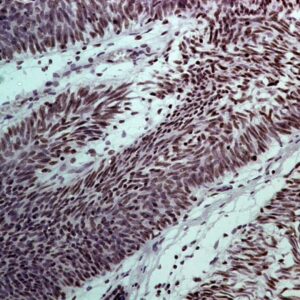

BioGenex has pioneered the development of miRNA research and diagnostics tools with leading-edge products. Currently, we offer over 240 ready-to-use (RTU) Super Sensitive™ Nucleic Acid (SSNA) miRNA ISH probes for accurate and early tumor diagnosis. These probes are sensitive enough to detect low-abundant miRNA(s) that are often required to identify biomarkers. They have a high melting temperature enabling stringent washes to remove non-specific binding. BioGenex miRNA probes are dual-end labeled with an anti-fluorophore to amplify the signal and yield clean and intense staining.